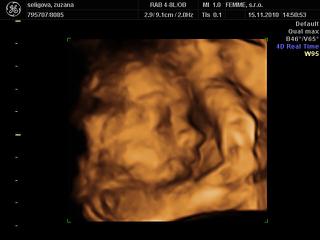

@bebulik aj moj chlap tvrdil, ze plodi len baby a vidis, ake gulky sa nam na uzv ukazali 😀